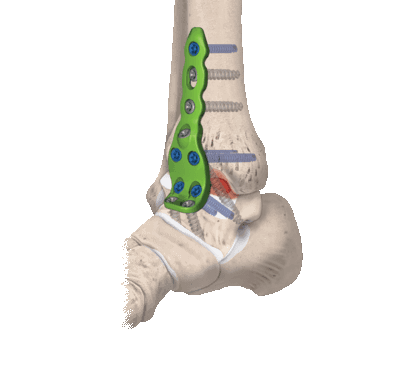

Артродез голеностопного сустава.

Ранее золотым стандартом хирургического лечения был артродез — операция, направленная на полное обездвиживание голеностопа. С одной стороны, она помогала избавиться от хронических болей. С другой — изменяла биомеханику стопы и всей конечности, из-за чего нарушалась динамика ходьбы и нередко возникала хромота. Поэтому от артродеза стали отказываться, а вместо него начали выполнять эндопротезирование.

- Внутрисуставный. В процессе хирургии выполняется вскрытие капсулы сустава с последующим удалением поврежденного гиалинового хряща с поверхностей костных элементов. После репозиции костей в выгодном положении выполняется их фиксация металлическими приспособлениями.

- Комбинированный. Эта техника подразумевает сочетание в одном хирургическом процессе двух способов: внутрисуставного и внесуставного. Так, хрящевые структуры с сустава полностью счищаются, внедряется аутотрансплантат, который фиксируют специальными металлическими пластинами.

- На нижнюю треть бедра накладывается пневматический жгут. Далее создают доступ, совершая скальпелем линейный кожный разрез вдоль сустава. Разрез равен примерно 10 см.

- На следующем этапе выполняется вскрытие и надежная супинация сустава, которая облегчит работу с очередными манипуляциями.

- Затем подготавливаются поверхности большеберцовой и таранной костей. Подготовка включает резекцию хрящевых тканей хирургическим долотом, удаление окостенения.

- Дальше стопа выводится из порочного положения. Большеберцовый элемент и таранный компонент плотно сопоставляют друг с другом в удобной с точки зрения физиологии позиции. Достигнутая позиция скрепляется металлической конструкцией необходимого типа.

- Используемые операционные ходы на завершающем этапе закрывают при помощи послойного ушивания мягких тканей с оставлением дренажа.

В случаях сильной деформации может быть применена остеотомия малой берцовой кости. Обширные костные потери возмещаются трансплантатами - фрагментами аналогичного биологического материала, взятыми у пациента из гребня повздовшной кости.

Если использовались наружные системы фиксации, например, аппарат Илизарова, гипсование не применяется. При установке внутренних металлических имплантов, на прооперированную конечность ставят гипс. До тех пор, пока анкилоз не состоится, пациент находится в гипсовой повязке. Скорость костного сращения у каждого отдельного пациента может отличаться в силу физиологических особенностей организма. Полностью срастается и обездвиживается сустав через 3-6 месяцев после операции.